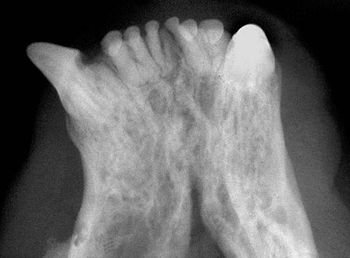

You see a possible lesion on a veterinary patient's dental film-here's how to tell if it's the real thing.

Intraoral radiography can help identify this pathology in your patients-and guide you toward the next step in your treatment plan.